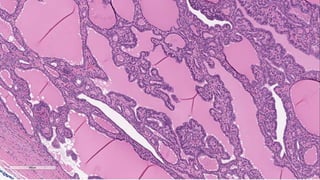

35 year Female with MNG

S-21612/2022

• Benign non-invasive encapsulated follicular-cell-derived neoplasm that is

characterized by an intrafollicular papillary architecture, lacks nuclear

features of PTC, and is often associated with autonomous hyperfunction.

• Activating TSHR mutations are detected in up to 70%

• GNAS mutations are found in a small subset- McCune Albright syndrome

• Increase in cyclic AMP (cAMP)

Follicular thyroid adenoma with papillary architecture